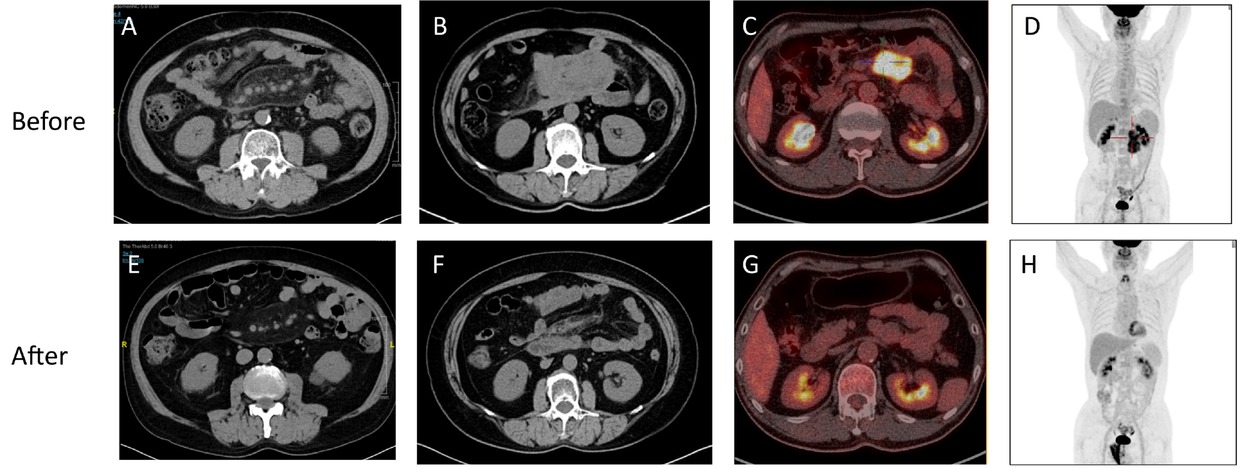

IgG4-SM exhibits characteristic imaging features. Abdominal CT axial images often reveal hazy shadows in the mesenteric region, indicative of mild inflammatory infiltration (see Figure 2A). In more severe cases, CT images may display irregular soft tissue masses, suggesting fibrosis and active inflammation (Figure 2B). PET-CT scans further reveal significant increases in 18F-FDG uptake within these soft tissue masses, reflecting high metabolic activity (Figure 2C-D).

Characteristic imaging findings of IgG4-SM before and after treatment. (A) Abdominal CT axial image of a patient with mild IgG4-SM showing hazy shadows in the mesenteric region. (B) Abdominal CT axial image of a patient with severe IgG4-SM showing irregular soft tissue masses in the mesenteric region. (C-D) PET-CT images of an IgG4-SM patient showing soft tissue masses in the mesenteric region with significantly increased 18F-FDG uptake, indicating high metabolic activity. (E-H) Post-treatment images corresponding to (A-D) demonstrate reduced lesion size, resolved hazy shadows, decreased soft tissue masses, and diminished 18F-FDG uptake, indicating a favorable treatment response.

Despite the potential difficulty in distinguishing IgG4-SM from malignancies on imaging, patients with IgG4-SM typically exhibit favorable radiological responses to corticosteroid therapy. Post-treatment imaging shows reduced lesion size, alleviation of hazy shadows, shrinkage of soft tissue masses, and decreased 18F-FDG uptake, indicating effective treatment (Figure 2E-H). Compared to previously reported cases of IgG4-SM, our cohort exhibits similar imaging characteristics.[18]